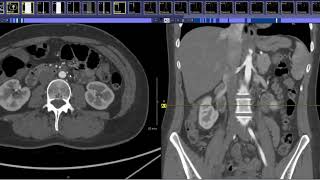

Gulfcoast Ultrasound Institute Instructor Emily Downs, BS, RDMS, RVT, RDCS, RT demonstrates how to evaluate the bifurcation of the aorta at the level of the distal aorta using ultrasound.